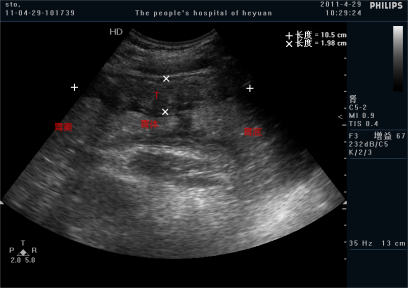

病例图:2011年11月,男,62岁,胃癌